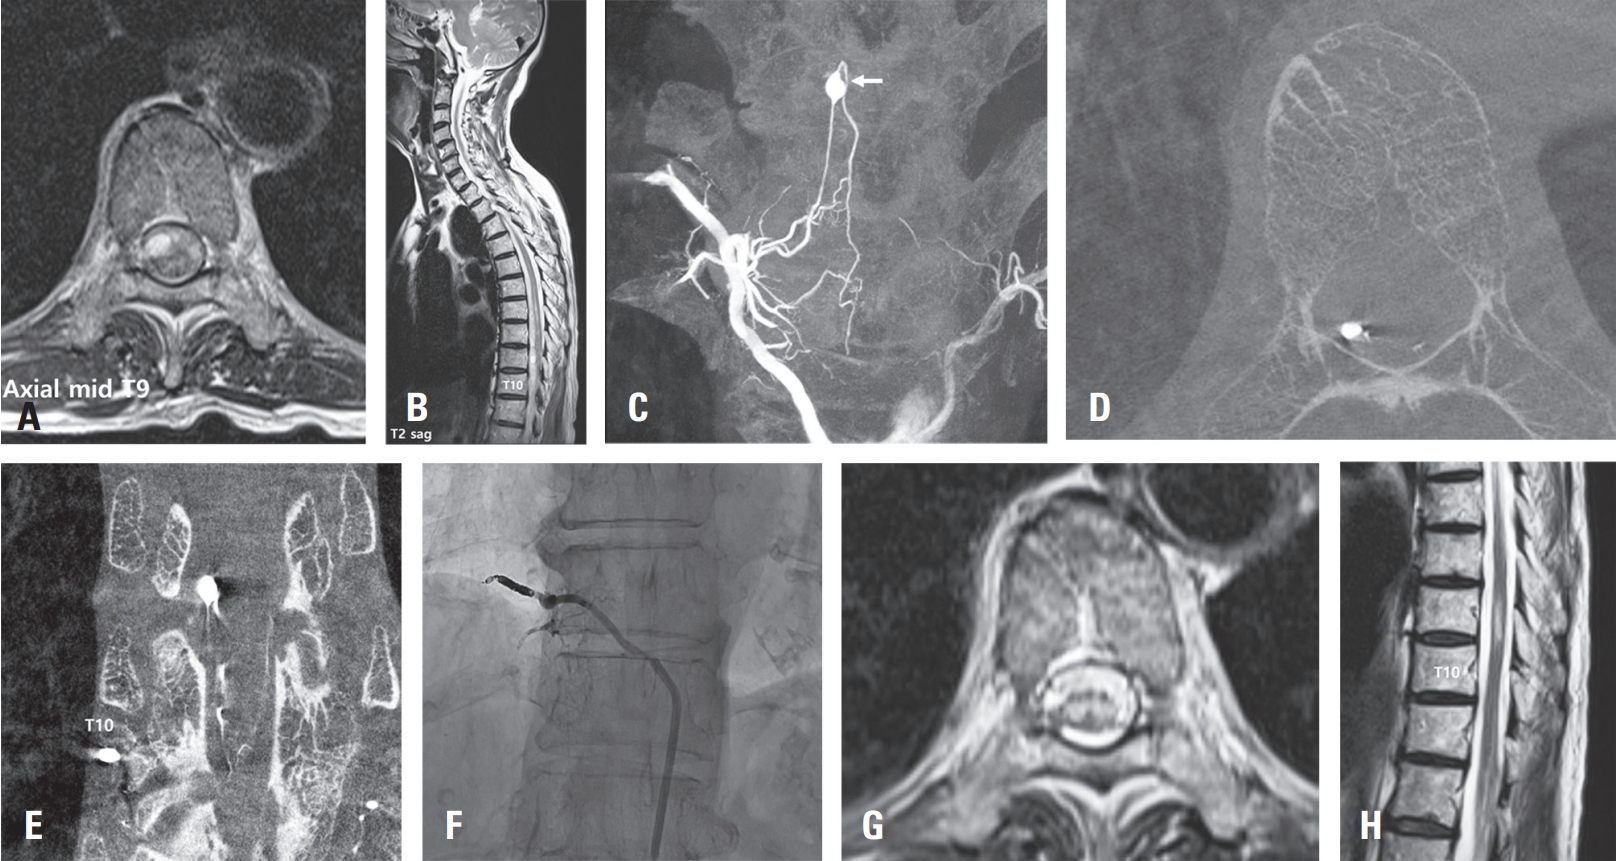

The patient then underwent surgical treatment on the subsequent day. Under general anesthesia, a total laminectomy was performed at thoracic levels 8 and 9, exposing the dura. After dural incision, a relatively small amount of subdural hematoma was identified, and a portion of it was removed. An acute bleeding focus was identified from the radicular artery beneath the left T9 nerve root. Following resection of the T9 root, the surrounding radicular artery was occluded with a clip for hemostasis. Postoperatively, the patient’s severe back pain significantly improved, and she was able to ambulate, leading to discharge in a walking state. Four weeks later, a follow-up Digital Subtraction Angiography (DSA) of the surgical site was performed, confirming the complete absence of the aneurysm (Fig. 2D).

Fig. 2.

Angiogram of the left T9 intercostal artery in the left anterior oblique view showing a focal fusiform dissecting aneurysm in left T9 radiculopial artery (A, arrow). 3-dimention reconstruction of CT angiogram showing 2 mmx2.5 mm sized aneurysm and network of vessels in relation to left T9 pedicle (B, C, arrow). Followup angiography was performed after POD 4 weeks and confirmed the non-visualization of aneurysm sac and feeding artery from left T9 radiculopial artery the complete absence of the aneurysm (D).

Fig. 2. Angiogram of the left T9 intercostal artery in the left anterior oblique view showing a focal fusiform dissecting aneurysm in left T9 radiculopial artery (A, arrow). 3-dimention reconstruction of CT angiogram showing 2 mmx2.5 mm sized aneurysm and network of vessels in relation to left T9 pedicle (B, C, arrow). Followup angiography was performed after POD 4 weeks and confirmed the non-visualization of aneurysm sac and feeding artery from left T9 radiculopial artery the complete absence of the aneurysm (D).